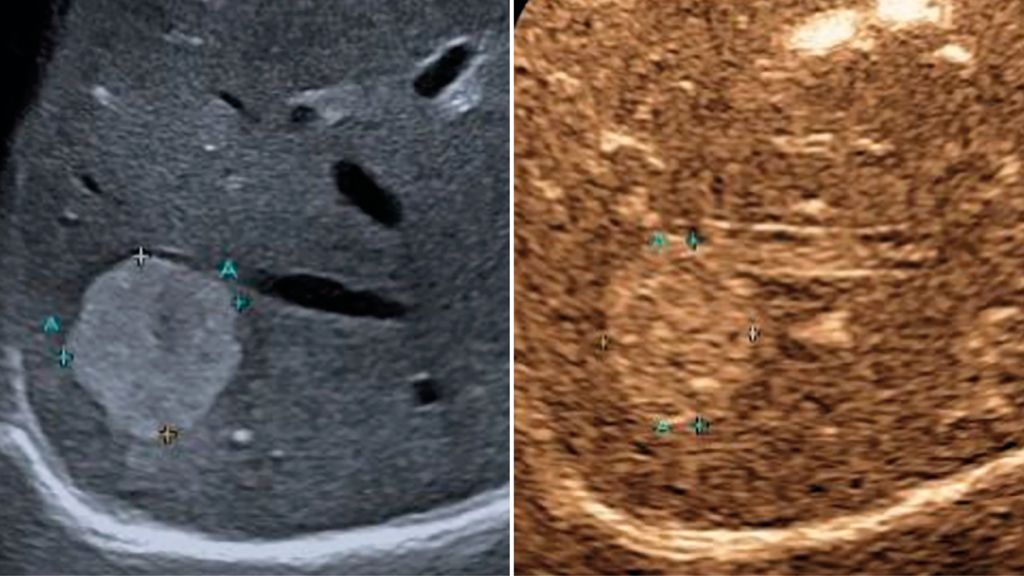

Trotz der hohen Aussagekraft moderner Ultraschallgeräte im B-Mode kann derzeit – mit Ausnahme des Screenings auf hepatozelluläre Karzinome bei chronischen Lebererkrankungen – kein generelles Leberscreening empfohlen werden.5 Die Mehrzahl fokaler Leberläsionen ist benigne, darunter fokale Steatosen, Zysten, Hämangiome oder fokale noduläre Hyperplasien (Abb.3). Maligne Raumforderungen sind in populationsbasierten Studien selten.6

Abb. 3: Darstellung einer fokalen nodulären Hyperplasie (FNH) in der arteriellen Frühphase nach Gabe von 1,2ml SonoVue® mittels CEUS (links) und in der mikrovaskulären Bildgebung (Canon®-superb „Microvascular imaging“-Modus), wo die Radspeichenstruktur besser zur Darstellung kommt